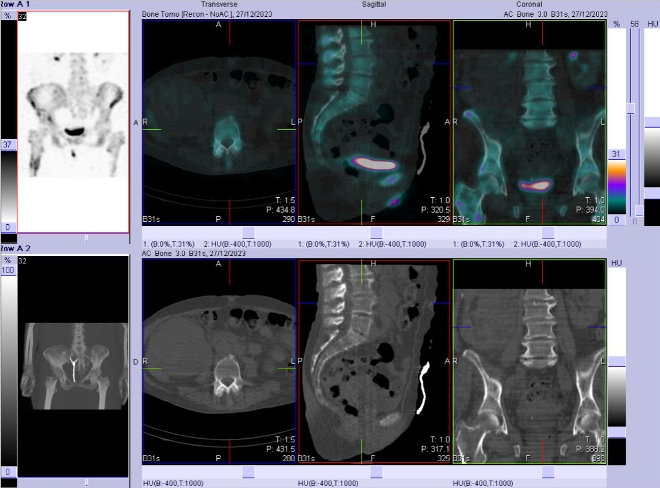

/ Obr. č. 8-10: Fúze obrazů SPECT a CT bederní páteře, pánve, kyčelních kloubů, proximální části stehenních kostí.

/

Popis:

Patologické ložisko vyšší osteoblastické aktivity v proximální části diafýzy pravé stehenní kosti. Osteolytická léze v kosti kyčelní vpravo těsně nad pravým kyčelním kloubem zasahující zčásti i do acetabula, na jejím mediálním okraji je vyšší osteoblastická aktivita.

Nález odpovídá metastatickému postižení skeletu (jak osteolytická, tak osteoblastická metastáza). Degenerativní změny páteře.